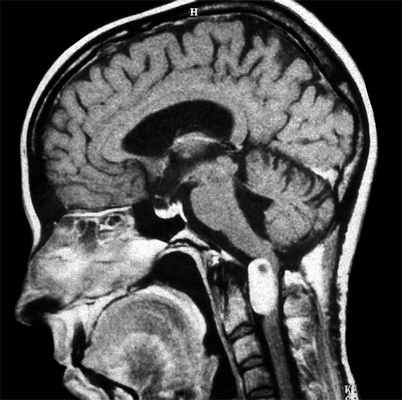

МРТ при опухоли мозга

В современном мире человечество подвержено онкологическим заболеванием. Рано или поздно организм дает сбой, и каждый из нас остерегается этой серьезной болезни. В некоторых системах организма развитие раковых клетках можно определить по ярко выраженным симптомам. Например, рак легких, желудочно-кишечного тракта или кожных покровов легко определяется на ранних стадиях при правильной диагностике.

Более опасным является развитие рака мозга. Данное заболевание может протекать незаметно на протяжении длительного времени. Зачастую онкологические заболевания головного мозга диагностируются на поздних стадиях, что и усугубляет процесс лечения. Причиной несвоевременной диагностики является бессимптомное протекание болезни и расположение опухоли внутри черепа. В некоторых случаях большие опухоли могут иметь более слабые симптомы, чем мелкие новообразования. Поэтому, до тех пор, пока у пациента нет ярко выраженных симптомов, он и не обращается к специалисту. Пациент попадает к доктору лишь при сильном ухудшенном самочувствии.

— Насколько эффективно МРТ при диагностике опухоли головного мозга?

Данный метод позволяет определить наличие опухоли на самых ранних стадиях. Если обнаружены признаки развития раковых клеток в головном мозге, пациенту вводят контрастный препарат для изучения распространения и степени онкологического заболевания. В результате диагностики врачи получают снимки новообразований с достаточно полной информацией: расположение, размер и форма. МРТ эффективно даже в случае наличия очень мелких опухолей, новообразований, расположенных вблизи кости или в стволе головного мозга. МРТ — надежный и эффективный метод диагностики онкологических заболеваний головного мозга.